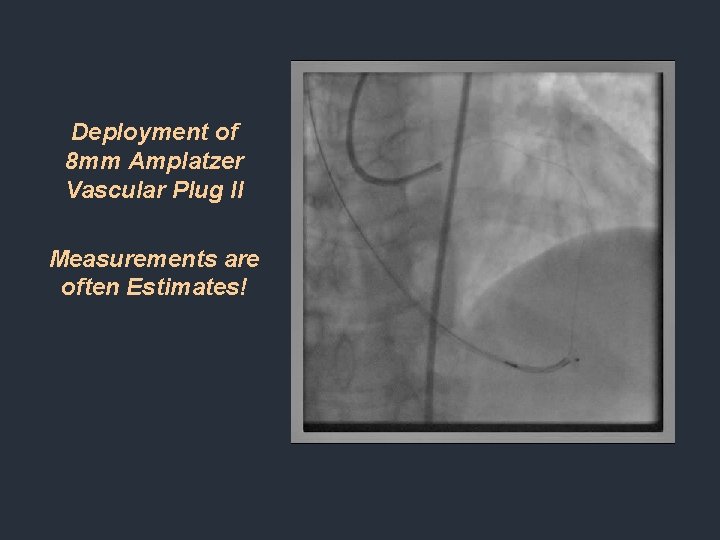

Deployment of 8 mm Amplatzer Vascular Plug II Measurements are often Estimates!

Redeployment Using 10 mm Vascular Plug II. Note all three discs are exposed